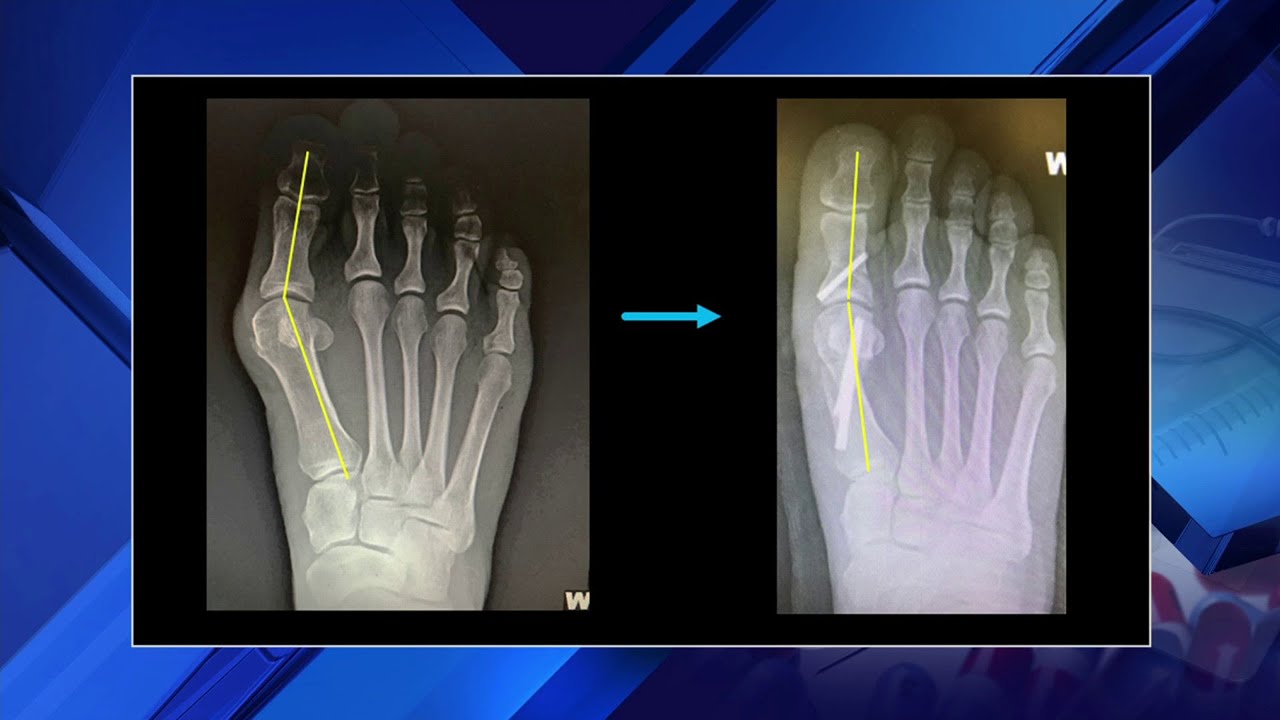

Surgery typically involves an osteotomy of the 1st ray to improve the alignment of the 1st metatarsal and great toe. However, the surgery can also be more complex and involve stabilizing the midfoot. We won’t get into that today but here’s an example of a typical surgical x-ray.